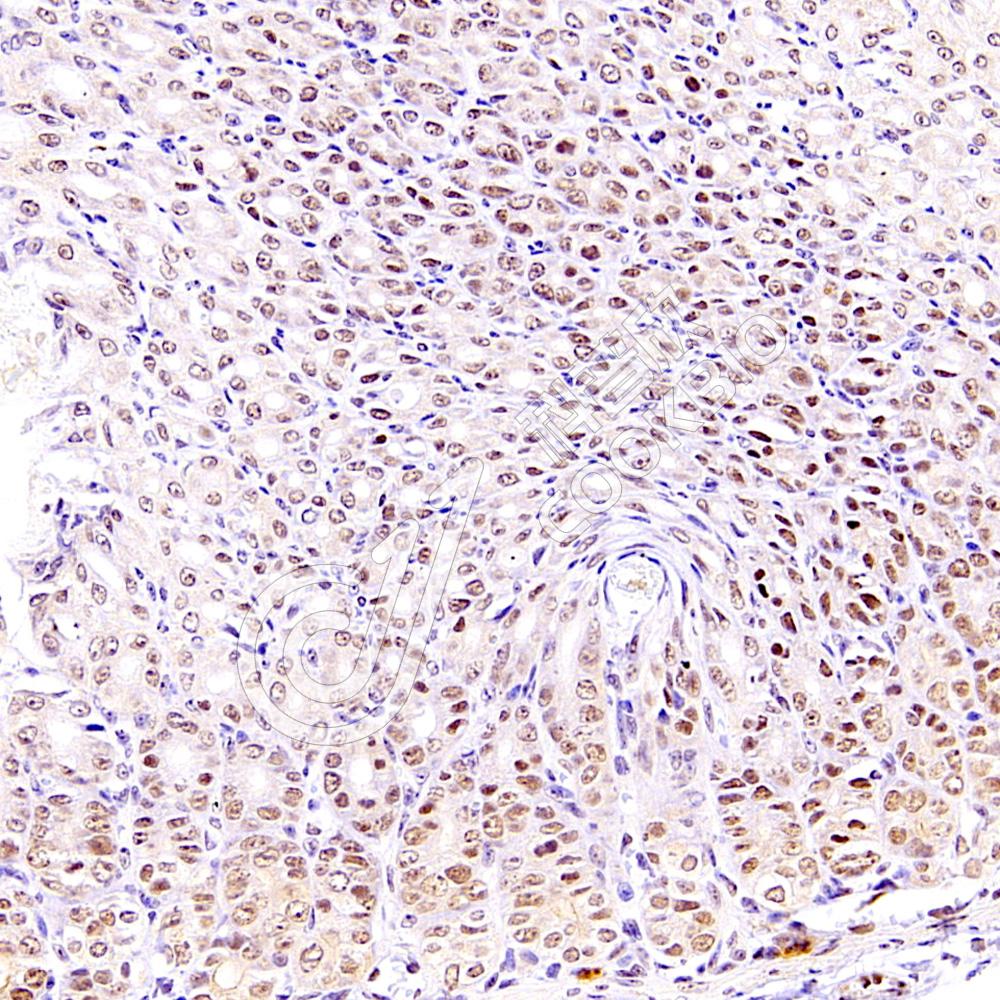

IHC检测Phospho-STAT3(Y705)蛋白(货号 K5450003).

样品: 人食管癌, 4%多聚甲醛 (货号KSG1101) 固定12-24小时.

抗原修复: Tris-EDTA抗原修复液(pH 9.0) (KSG1203), 98℃, 20分钟.

—抗: 1: 1300稀释, 4℃ 孵育过夜.

二抗: S-vision免疫组化多聚二抗(山羊抗兔),即用型 (货号KB3906), 室温孵育20分钟.